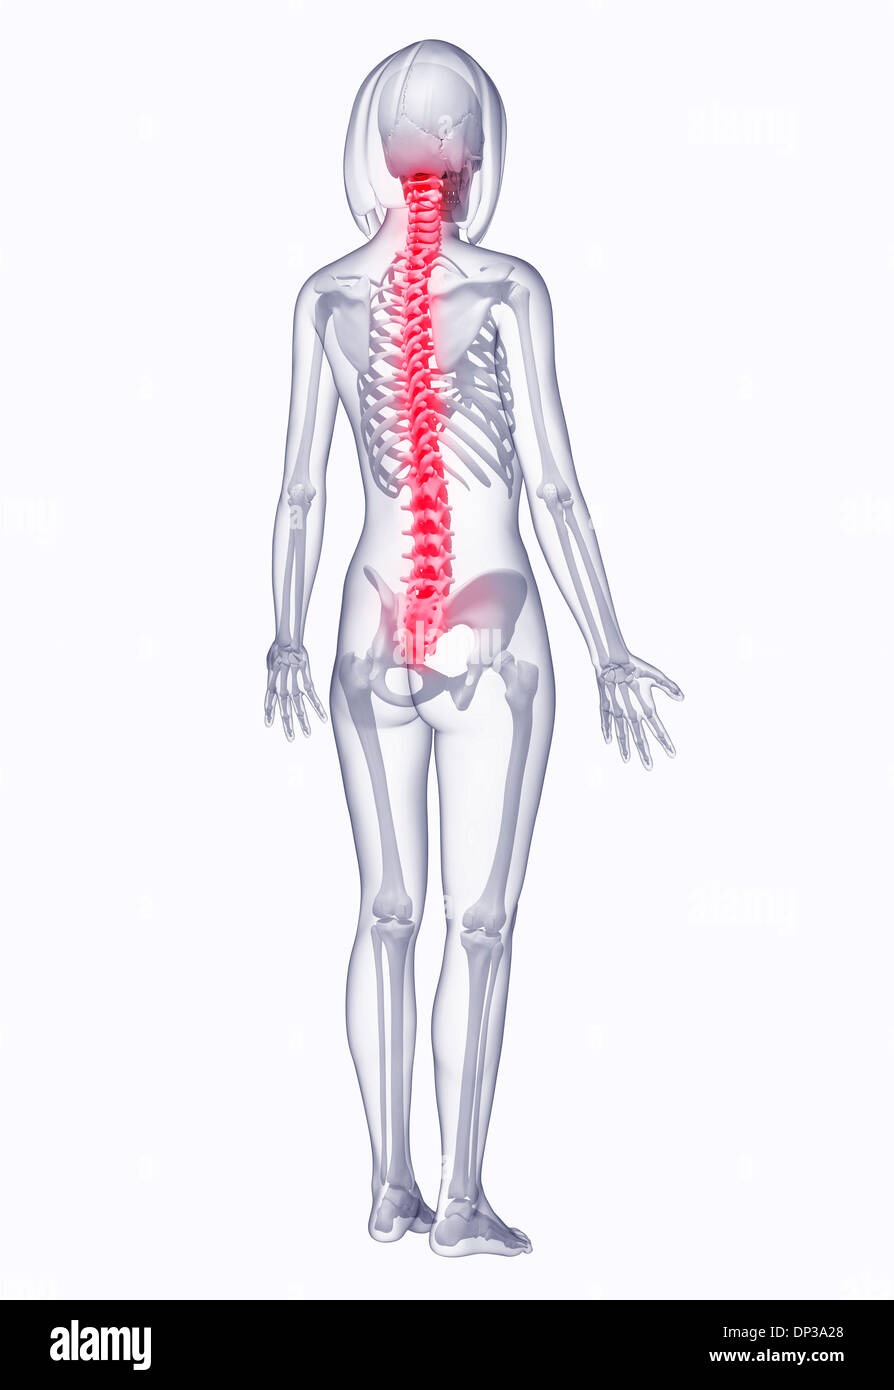

Back pain, artwork Banque D'Imageshttps://www.alamyimages.fr/image-license-details/?v=1https://www.alamyimages.fr/back-pain-artwork-image65227296.html

Back pain, artwork Banque D'Imageshttps://www.alamyimages.fr/image-license-details/?v=1https://www.alamyimages.fr/back-pain-artwork-image65227296.htmlRFDP3A28–Back pain, artwork